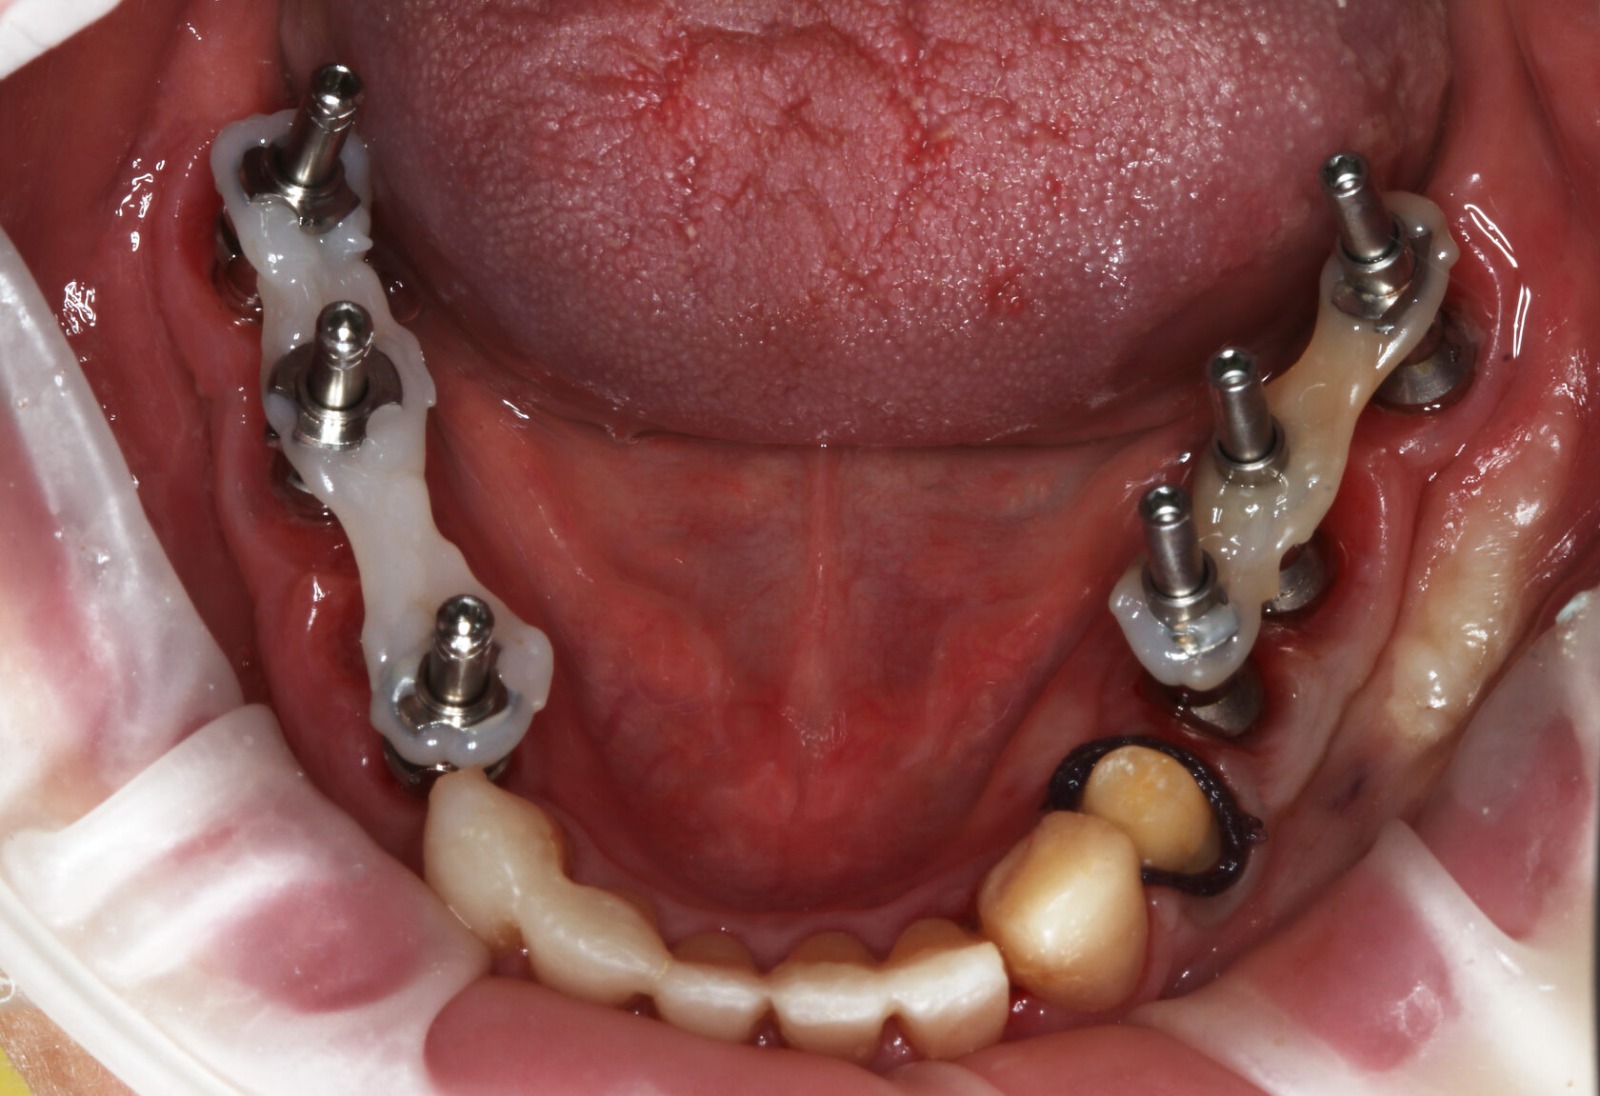

Фотографии учебного материала